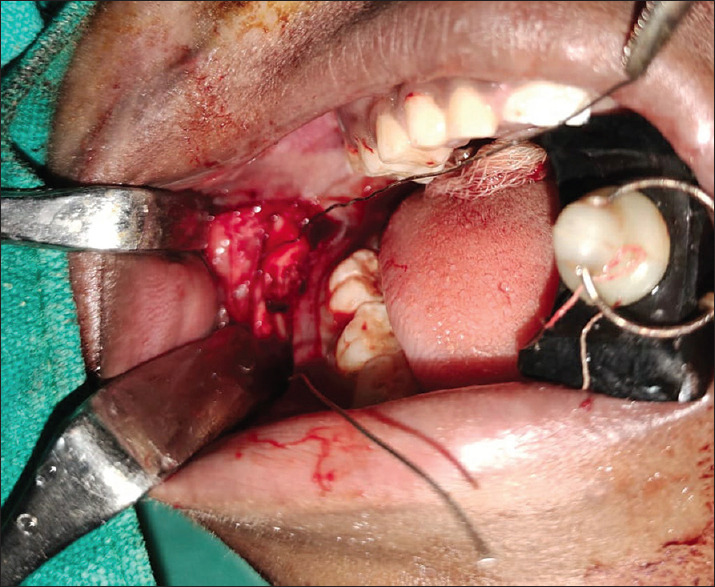

Technique: After raising a full-thickness mucoperiosteal flap, the fracture segments are identified and reduced. 1.6mm drill bit is used to make holes through the buccal cortex on either side of the fractured segment in an anteroposterior direction. The patency of holes is checked by passing a long 26-gauge wire. The proximal end of the wire is bent into a loop, a 2-0 resorbable polyglactin suture (vicryl) is passed through this loop and the loop is pressed in place to lock the suture. The wire with the attached suture is pulled through the distal end. Once the suture is secure in place, the 26G wire is cut, and the two ends of sutures are knotted and stabilised. The mucoperiosteal flap is then closed.